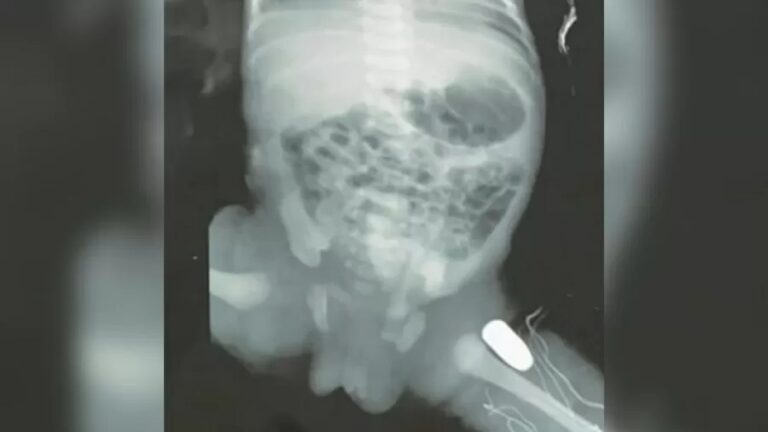

Uma adolescente de 15 anos passou por um parto de emergĂȘncia apĂłs ser baleada na barriga em Imperatriz (MA). A bala ficou alojada na perna da bebĂȘ.

Imagem: TV Globo/Reprodução

A garota, gråvida de 33 semanas, foi baleada na noite do domingo (16). Ela foi levada ao Hospital Materno Infantil de Imperatriz. Autoridades não informaram as circunstùncias na qual a garota foi baleada.

Recém-nascida deve passar por cirurgia nesta segunda-feira (17). Não hå detalhes sobre a extensão do ferimento na criança. Ao UOL, um parente da adolescente informou que as duas passam bem.